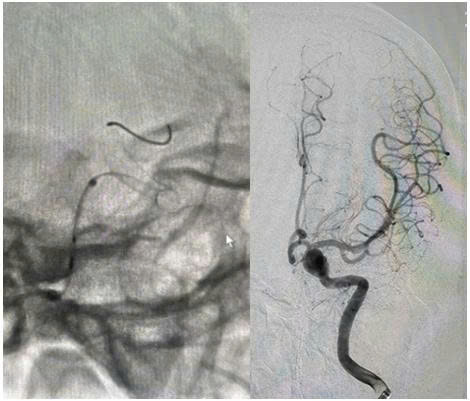

Quá trình can thiệp được thực hiện qua động mạch đùi phải theo phương pháp Seldinger. Bệnh nhân được chụp mạch não để đánh giá chính xác túi phình. Ê-kíp đã đặt thành công stent chuyển dòng kích thước 4,25 × 20 mm qua cổ túi phình động mạch cảnh trong trái đoạn động mạch mắt. Hình ảnh sau can thiệp cho thấy stent áp sát thành mạch, che phủ hoàn toàn cổ túi phình, giảm rõ rệt dòng máu vào túi phình, đồng thời đảm bảo tưới máu não tốt, tuần hoàn não trước đạt TICI 3.

Hình ảnh thả stent chuyển dòng túi phình lớn ở động mạch cảnh trong trái dưới DSA